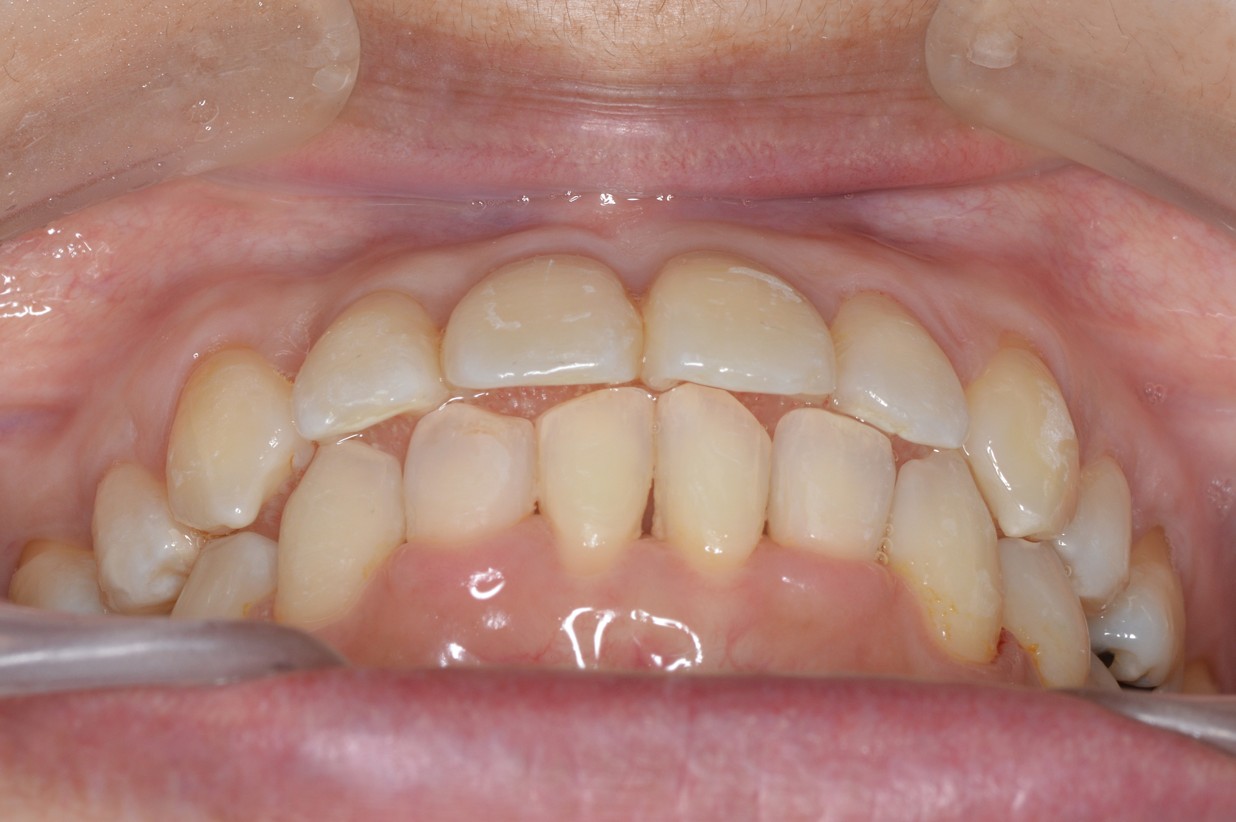

症例2

| 項目 | 詳細 |

|---|---|

| 患者様データ | 30代 女性 |

| 来院時の主訴 | 「右上の、内側に生えている歯が邪魔。」 |

| 矯正法 | 上の歯2本、下の歯2本、親知らず3本を抜歯しての矯正 |

| 通院期間 | 3年6ヶ月 |

| 治療費 | 総額:1,230,000円(税抜) 【内訳】 精密検査50,000円、メタルワイヤー矯正800,000円、月に1度の調整料5,000円、後戻り防止のリテーナー35,000円×2 |

| リスクと副作用 |

①歯を動かす事による痛みがあります。また、装置に慣れるまでは、口内炎ができやすいです。 ②歯肉が退縮するリスクがあります。装置が全ての歯に付くので、ハミガキが難しくなります。 ③長期的なメインテナンスが必要 |

| ここがこだわりのポイント!☝ | こちらの患者様は上の歯が1本内側に生えていましたが、奥歯の噛み合わせの方が問題でした。ハサミ状咬合といい、奥歯が極端に外側に向いており、下の歯と噛み合っていない状態でした。ハサミ状咬合は長期的にみると、前歯に大きな負担がかかったり、磨きにくい事による虫歯や歯周病になりやすいなどのリスクがあります。治療期間はかかりましたが、見た目の良さだけでなく、機能的にも改善しました。 |